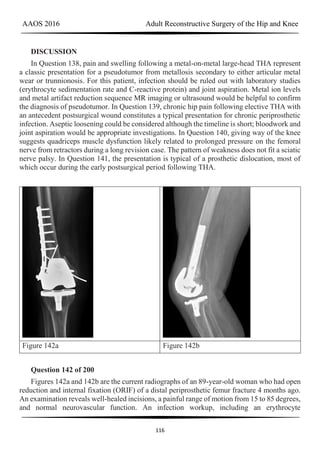

Figure 60a Figure 60b Figure 60c

Figure 61 Figure 62a Figure 62b

RESPONSES FOR QUESTIONS 58 THROUGH 62

Total knee arthroplasty (TKA) is performed to address each condition shown in Figures

58 through 62b. Which complication is most commonly associated with each image?

Question 60 of 200

Figure 60a through Figure 60c

PREFERRED RESPONSE: 2- Skin necrosis

Question 61 of 200

Figure 61

PREFERRED RESPONSE: 5- Anterior knee pain

Question 62 of 200

Figure 62a and Figure 62b

PREFERRED RESPONSE: 6- Malalignment

DISCUSSION

Figure 58 reveals a posttraumatic valgus deformity. Correction of valgus with lateral soft-

TKA to centralize the extensor mechanism. Figures 60a (anteroposterior [AP] view) and 60b

(lateral view) reveal a fused knee in full extension.

TKA after fusion is associated with multiple complications including skin necrosis,

infection, and instability. The skin is contracted because of limited knee motion and has

multiple scars (Figure 60c). Mobilization of the skin during and after knee arthroplasty can

place excess tension on the soft tissues, resulting in skin necrosis and infection. Treatment

consisting of prompt debridement and soft-tissue coverage, usually with medial gastrocnemius

muscle transposition, is required. Figure 61 shows a knee with prior tibial tubercle fixation

and marked patella infera. Shortening of the patellar ligament is associated with restricted knee

motion. This may necessitate more extensile exposure using tibial tubercle osteotomy or rectus

snip during TKA to obtain adequate surgical exposure. The inferior position of the patella can

cause impingement between the patellar component and tibial insert, resulting in anterior knee

pain. Restoring a more normal position of the patella may necessitate distal positioning of the

femoral component as well as tibial tubercle osteotomy with proximal recession of the

osteotomized tibial tubercle. Figures 62a (AP view of the distal femur) and 62b (AP view of

the proximal femur) show a posttraumatic deformity with a large retained intramedullary rod.

There is a varus distal femoral deformity that is not severe enough to necessitate extra-articular

corrective osteotomy. However, intramedullary hardware precludes use of conventional

intramedullary instrumentation, so computer navigation or patient-specific cutting guides will

be necessary to orient the bone cuts and avoid implant malalignment.